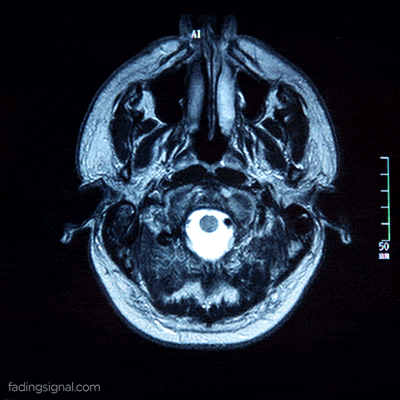

C’est ce que confirme une étude publiée en 2017 dans la revue Nature. À travers une résonnance magnétique, l’équipe de chercheurs qui a réalisé cette étude a pu observer des changements dans certaines parties du cerveau liées à l’orientation.